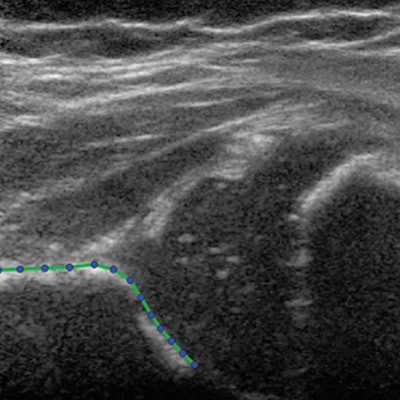

Statistical shape modeling can quantify the shape of the acetabulum on ultrasound images. Bonsel et al said using ultrasound images can render more data for development of the hip than angle measurements alone.

The modeling created several shape modes from the 13 landmarks placed on ultrasound images of each hip. These modes showed shape variations of hip shapes on imaging sets.